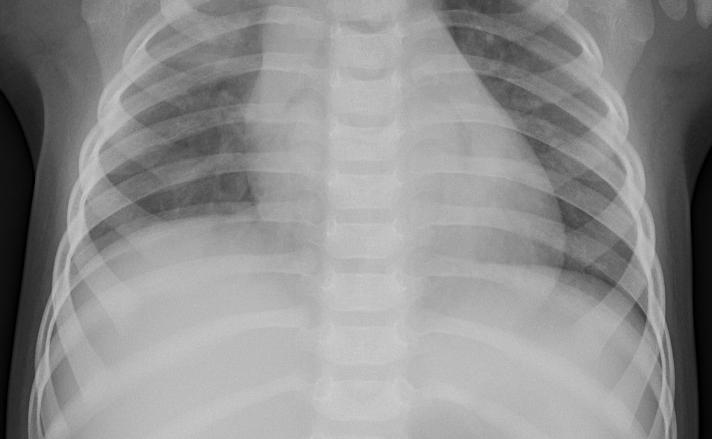

We conduct human subject experiments on two image classification datasets: a natural image dataset, Butterflies v.s. Moths (BM) and a medical image dataset of chest X-rays (CXR). For BM, we followed Singla et al. (2014) and acquired 200 images from ImageNet Krizhevsky et al. (2012). BM is a binary classification problem and each class contains two species. CXR is a balanced binary classification subset taken from Kermany et al. (2018) with 3,166 chest X-ray images that are labeled with either normal or pneumonia. We randomly split the datasets following 60%:20%:20% ratio. The classification accuracy with our base supervised learning models are 97.5% for BM and 97.3% for CXR. We only present results with human subjects in the main paper, but results from simulation experiments with TML as a synthetic agent, such as filtering triplets providing better results, are qualitatively consistent. See §D and §E in the appendix for more details.

5.3 Results on Chest X-rays

We use the same experimental setup as BM to evaluate HC and MLE representations in CXR.

H2H comparison results show HC NI examples are slightly preferred over MLE NI examples but the difference is not statistically significant. We recruit 50 Prolific workers to each make 20 H2H comparisons between HC NI examples and MLE NI examples. The mean preference for HC over MLE is 0.516 with a 95% confidence interval of ±0.0725plus-or-minus0.0725\pm 0.0725 (p=0.379𝑝0.379p=0.379 with one-sample t-test). H2H comparison in CXR is especially challenging as laypeople need to differentiate between two chest X-rays in the same class, hence the slightly worse performance in H2H compared to BM.

Similar to BM, HC outperforms MLE in both neutral and persuasive decision support in CXR. As expected, Fig. 4(b) shows that pneumonia classification is a much harder task than butterfly vs. moth classification, indicated by the lower accuracies across all conditions. In neutral decision support, HC enables much better accuracy than MLE (79.1% vs. 63.8%, p=2e8𝑝2e8p=2\mathrm{e}{-8} with two-sample t-test). In fact, similar to the BM setting, MLE provides similar performance with RIRO (63.8% vs. 65.9%, p=0.390𝑝0.390p=0.390), suggesting that MLE representations are no different from random representations for selecting nearest neighbors within a class. To contextualize our results, we would like to highlight that our crowdworkers are laypeople and have no medical training. It is thus impressive that human-compatible representations enable an accuracy of almost 80% in neutral decision support, which demonstrates the potential of human-compatible representations.

In persuasive decision support, HC provides the highest decision support accuracy at 90.0%, also much higher than MLE at 77.0% (p=2e10𝑝2e10p=2\mathrm{e}{-10}). Again, while we do not recommend persuasive decision support as a policy for decision support in practice, these results show that our human-compatible representations are indeed more compatible with humans than MLE representations.